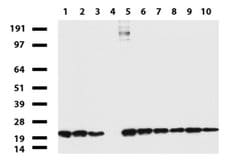

NME1 Mouse anti-Canine, Human, Rat, Clone: UMAB94, liquid, UltraMAB™

NME1 was identified because of its reduced mRNA transcript levels in highly metastatic cells. Nucleoside diphosphate kinase (NDK) exists as a hexamer composed of ′A′ (encoded by this gene) and ′B′ (encoded by NME2) isoforms. Mutations in the gene have been identified in aggressive neuroblastomas. Two transcript variants encoding different isoforms have been found for this gene. Co-transcription of this gene and the neighboring downstream gene (NME2) generates naturally-occurring transcripts (NME1-NME2), which encodes a fusion protein comprised of sequence sharing identity with each individual gene product.Specifications

| Immunocytochemistry, Immunofluorescence, Immunohistochemistry (Paraffin) | |